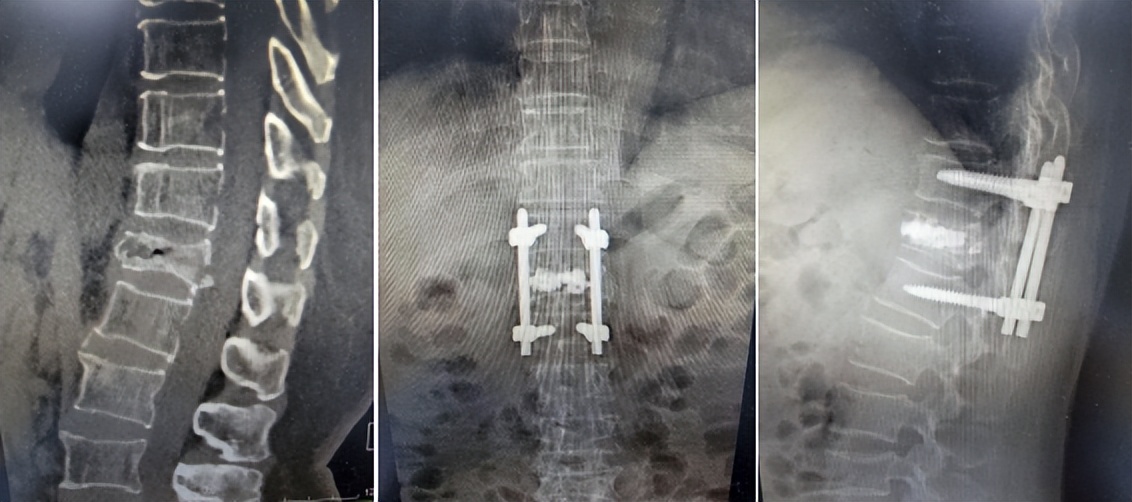

60多岁的龚阿姨来自本省外市,因不慎摔倒,造成胸12椎体爆裂骨折,椎体压缩严重(超过了椎体高度的二分之一),当地医院计划给予实施椎体成形术,但因考虑其骨折椎体碎裂严重,手术“骨水泥”渗漏风险较大,而且患者椎体压缩超过椎体高度的二分之一,单纯椎体后凸成形手术恐难以恢复高度,造成患者脊柱后凸畸形,故当地医院未能按计划手术。为难之际,龚阿姨通过家人了解到苏州高新区人民医院脊柱微创治疗中心成功治疗了许多此类骨折病人,于是,其家人满怀希望地带着她前来该院就诊。

该院骨科脊柱疾病微创治疗中心主任刘勇博士仔细看了患者资料后,认为可以采用“椎弓根钉棒技术结合椎体后凸成形术”这种杂交手术进行治疗。经过前期精心规划、细致准备,手术如期进行。术中,刘勇主任团队先采用椎弓根钉棒进行固定,并复位压缩的胸12椎体;然后,分别于骨折压缩椎体两侧椎弓根注入骨水泥,填充爆裂骨折的骨缺损处,最大限度地恢复了椎体的高度,而且通过骨水泥获得了脊柱的即刻稳定性。手术很成功。术后一周,龚阿姨就在佩戴保护支具下开始下地行走了,她的脸上终于露出了久违的笑容。